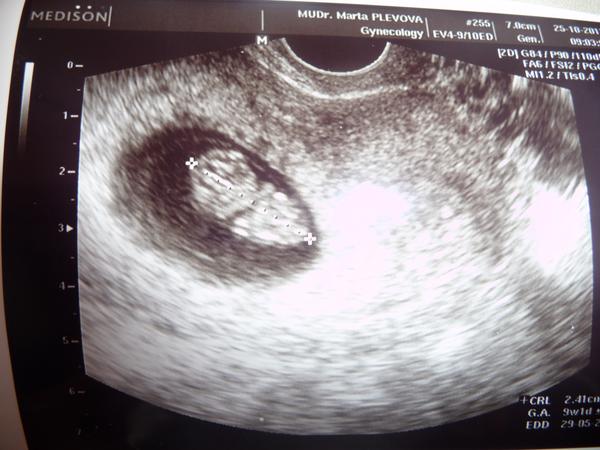

nase malinke ma 2,41 cm a bol to 9tt+2 nastavila som si uz, ze sa nesnazime ale neviem preco mi to neukazuje...

@tusinka dakujeme budeme sa snazit 🙂 hej krasnu fotecku nam spravila pekne zvacsenu aj babo pekne vidno zda sa velke ale ma len 2,41cm ale vytesujem sa z nej stale 😀 no s tym jedenim je to take vselijake co ti poviem jest musim sice na silu ale co uz ...hm no toto zaujimave ako si telo robi co chce mozno prave pre tu ovu ta vseto bolelo ale niekedy ti staci sa snazit aj pred nou spermia prezije par dni takze este nehadz flintu do zita 🙂 vies co ani nie mam ho sice take nafuknute ale nevyzeram este tehotna 😀